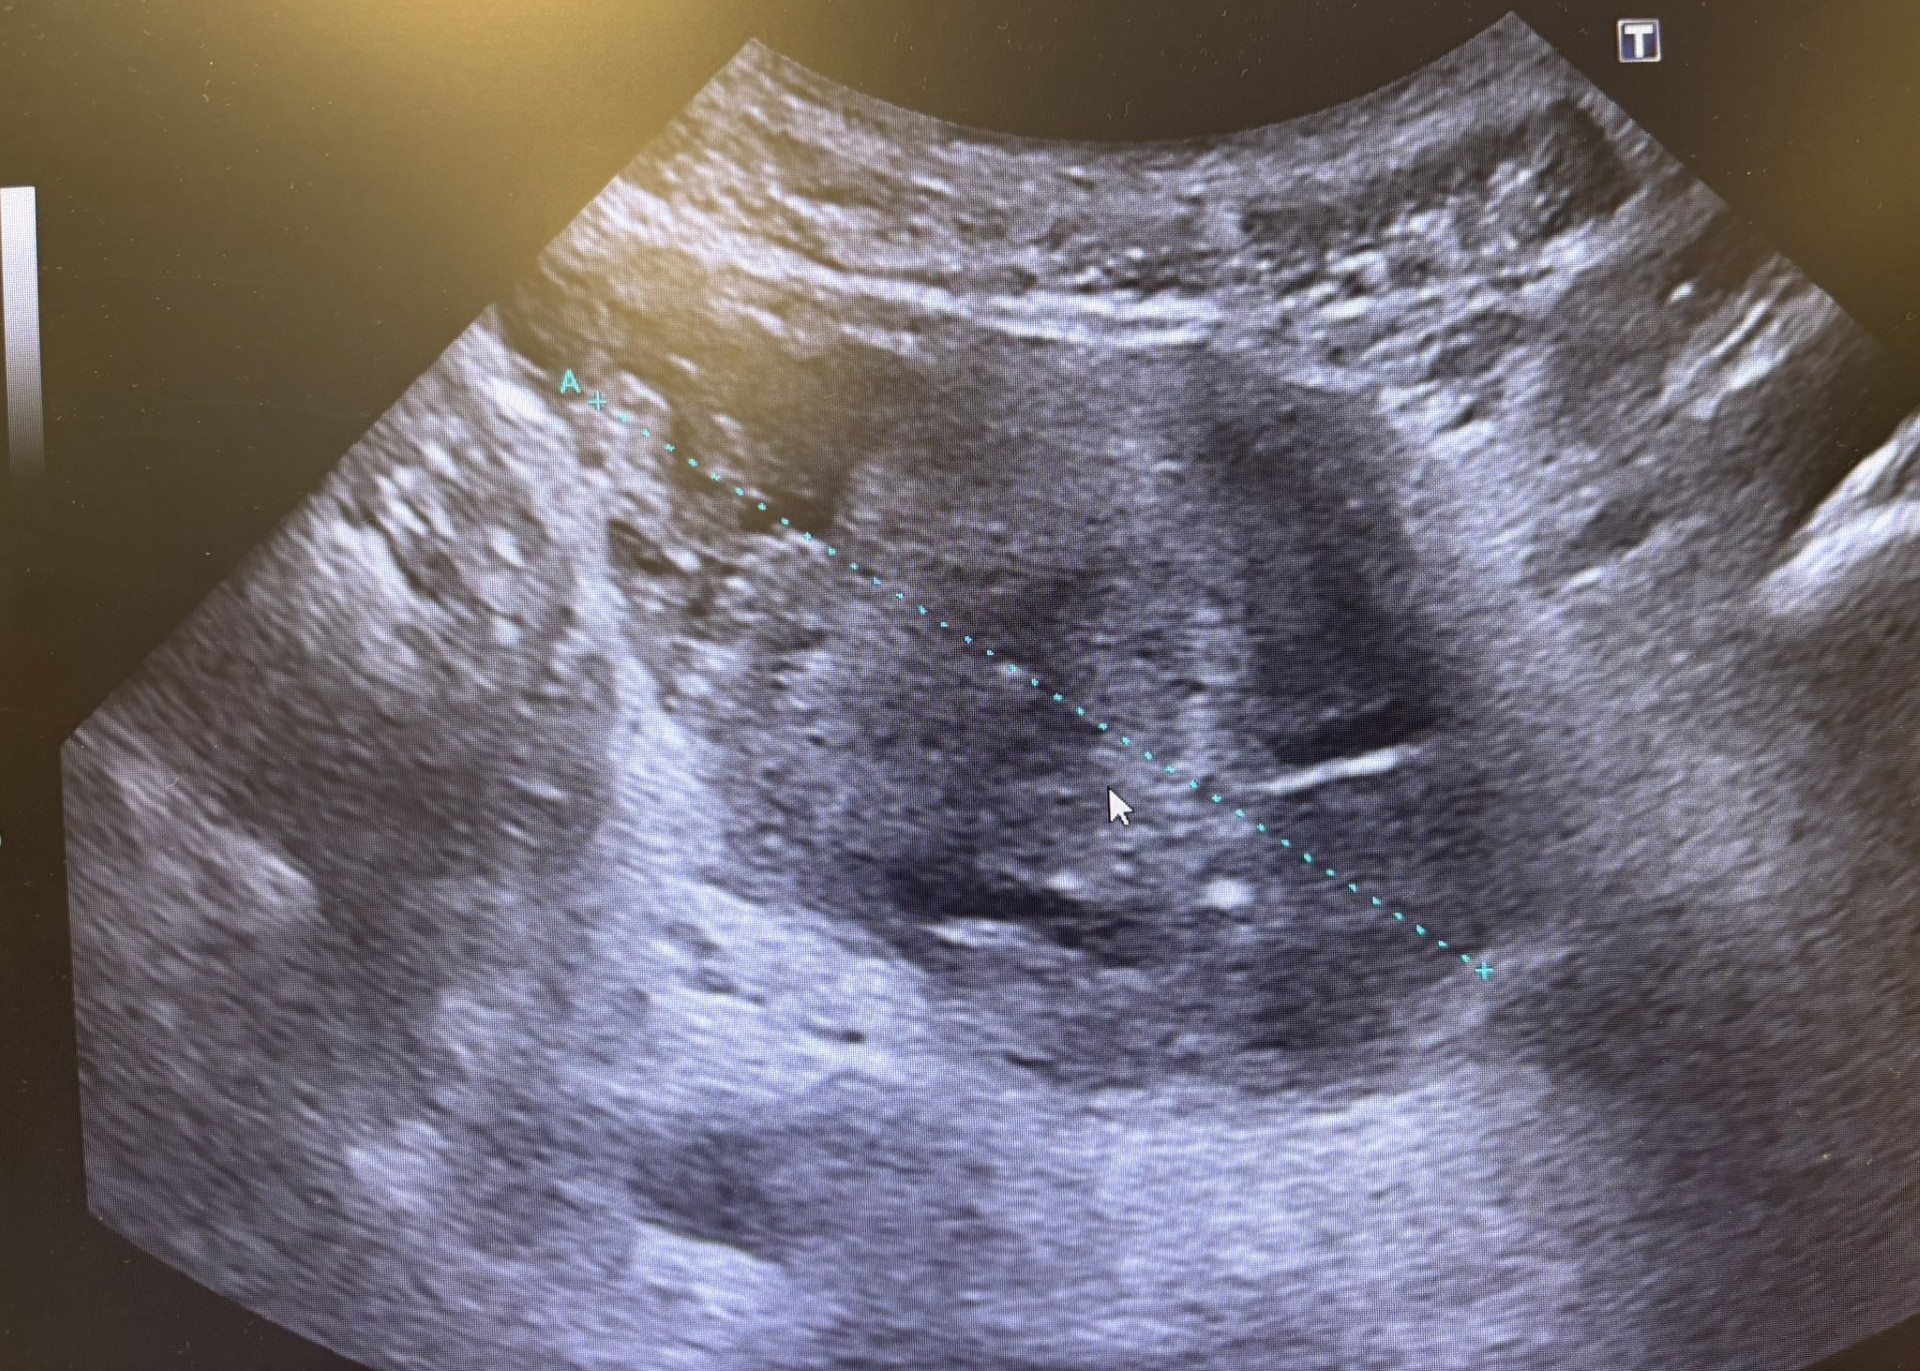

Presentamos el caso de un varón de 62 años fumador crónico (40 paquetes/año) que consulta por síndrome miccional sin fiebre de 20 días de evolución, caracterizado por tenesmo vesical, polaquiuria y hematuria. Había sido tratado previamente con cefixima sin mejoría clínica. En atención primaria se aisló Staphylococcus haemolyticus resistente a meticilina en urocultivo, por lo que fue derivado a urgencias. A su llegada se encontraba afebril y normotenso, con leve dolor abdominal a la palpación y retención urinaria. La analítica mostró leucocitosis (10.720/mm³), neutrofilia y elevación de PCR. El sedimento urinario reveló leucocituria, hematuria y bacteriuria. Ante la persistencia de síntomas y la presencia de retención urinaria se realiza ecografía vesicoprostática en Urgencias objetivándose masa sólida intravesical, irregular con base ancha y vascularización aumentada en Doppler, sugestiva de neoplasia vesical.

Derivación preferente a Urología con informe y registro de imágenes ecográficas.

Se realizó una resección transuretral. El informe operatorio describe una masa vesical que ocupa todo el trígono y parte de la cara lateral derecha, claramente infiltrante. Se solicitó TAC toracoabdominal y pélvico para estudio de extensión.